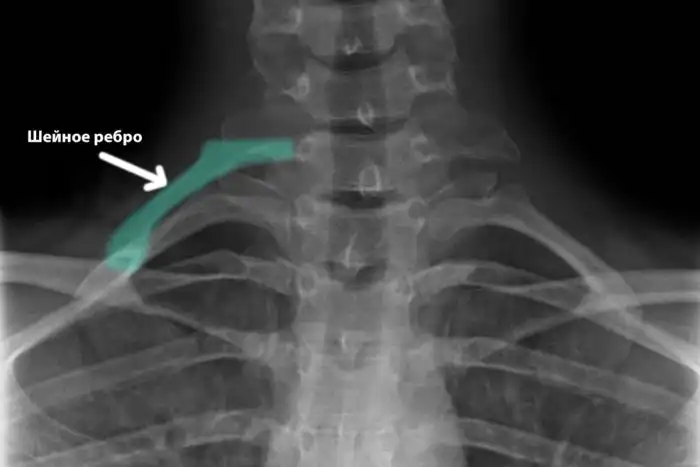

Менее 1% имеет «лишние» шейные ребра, доставшиеся от рептилий.